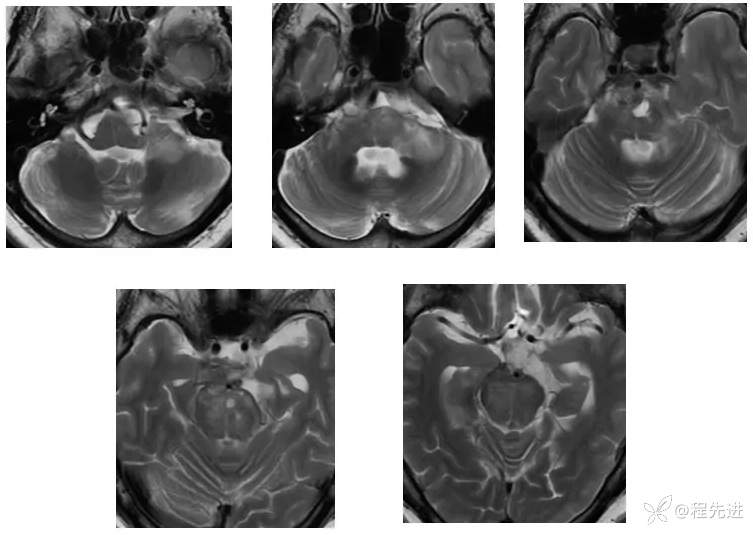

【现病史及既往史】:右眼斜视及视力下降7个月,右眼脸下垂3个月,右眼失明1个月

查体:生命体征平稳,右眼脸下垂,右眼失明,左眼内收位,外展受限,光反应迟钝,左侧角膜反射减弱,左侧听力下降,左面部痛温觉减弱无吞咽困难,无饮食饮水呛咳,伸舌舌尖左偏。